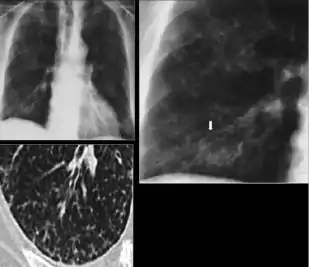

2. Any cavitary lesion - Lucency (darkened area) within the lung parenchyma, with or without irregular margins that might be surrounded by an area of airspace consolidation or infiltrates, or by nodular or fibrotic (reticular) densities, or both. The walls surrounding the lucent area can be thick or thin. Calcification can exist around a cavity.

Chest X-ray of a person with advanced tuberculosis: Infection in both lungs is marked by white arrow-heads, and the formation of a cavity is marked by black arrows.